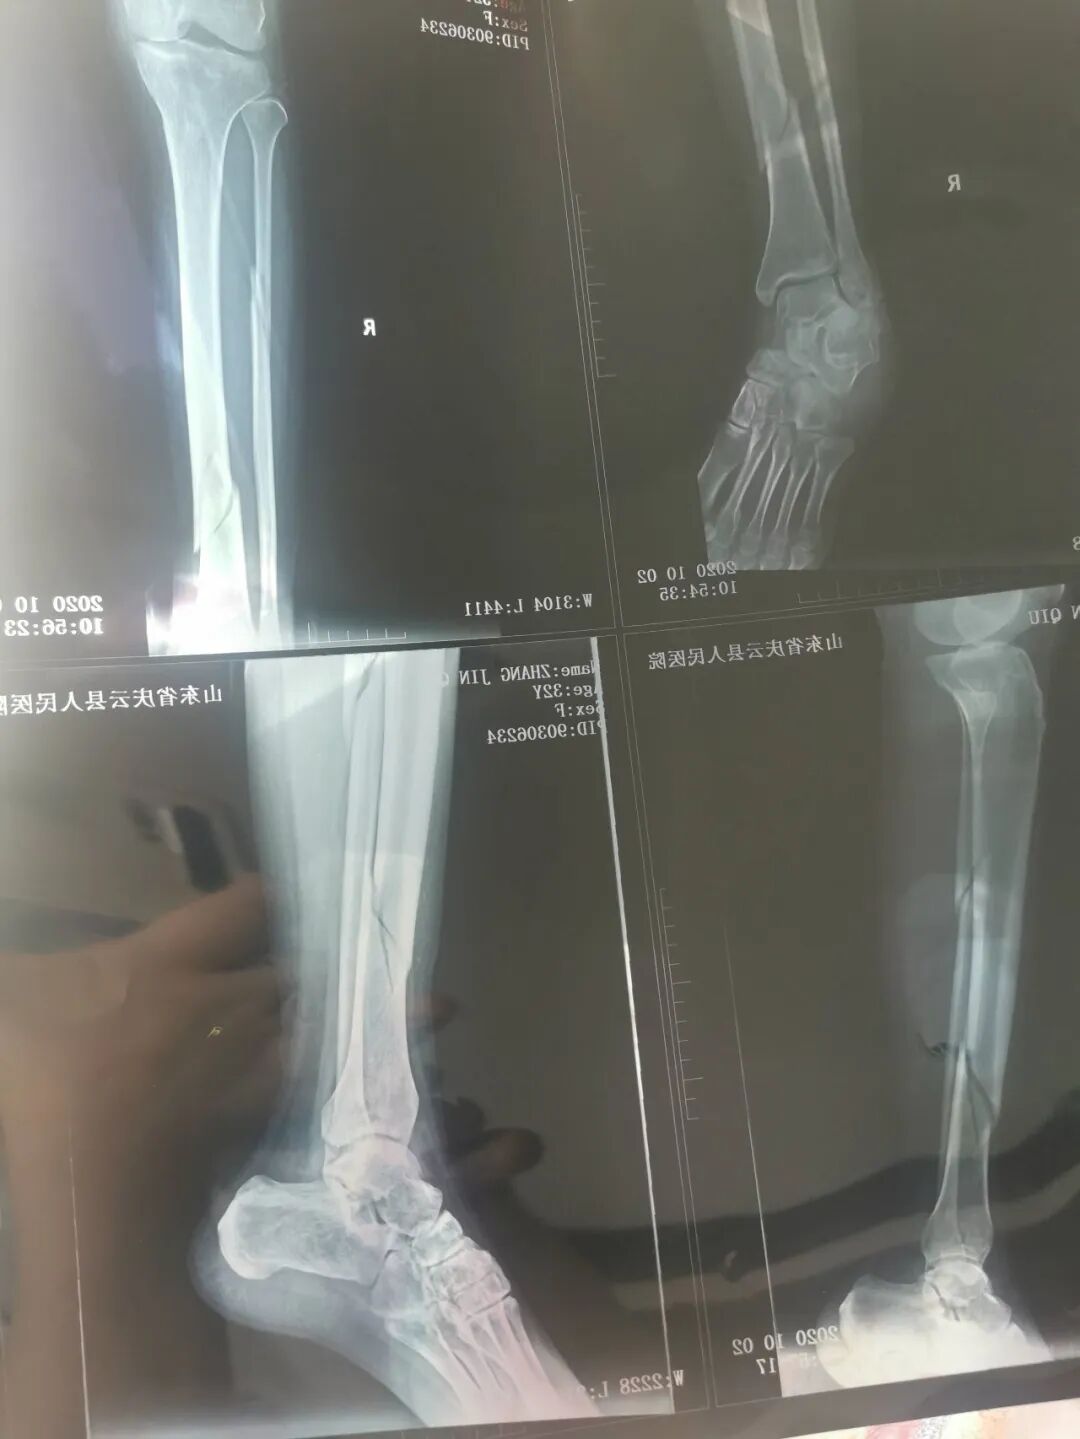

2019年10月,扶着助行器的小秋,在老家挪动时不慎摔倒。长期服用激素导致的骨质疏松,让她的小腿当场摔成两截。

“俺这个病不能打麻药,没法做手术。”这意味着,她只能保守治疗。当时的小秋陷入了绝望,心里总想“为什么倒霉的总是我?”。这次骨折,也让她彻底与轮椅为伴。

庆云县人民医院确诊骨折